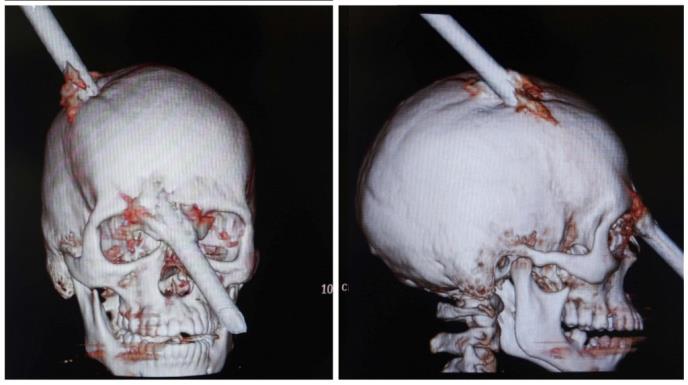

Potpuno svestan šipku dugu 1,8 metara, koja mu je probila lobanju, pridržavao je rukom

Usred radnog dana na gradilištu na glavu mu je s 5. sprata pala šipka duga 1,8 metara koja mu je kao nožem probila potiljak, prošla kroz glavu i izašla na čelo, tačno između očiju, prenosi Gardijan pisanje Hafington posta.

Lekari i dalje ne mogu da veruju da je mladić sve vreme bio svestan kao i da je lekarima hitne pomoći sam ispričao šta mu se dogodilo.

Štaviše, šipku je pridržavao vlastitom rukom. Odmah je operisan, a operacija je trajala pet sati.